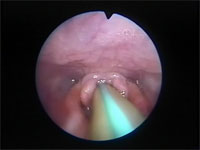

Abb 15 Mandrin-vor-Rima

Abbildung 15: Mandrin vor der fast geschlossenen Rima glottidis.

Abb 16 Mandrin-überwindet-Rima

Abbildung 16: Mandrin hat die Stimmritze passiert und wird intratracheal vorgeschoben.

Über diesen Mandrin kann im zweiten Schritt ein ebenfalls mit wenig Lidocain-Gel präparierter Plastiktrachealtubus von 2,5 bis 3,5 mm innerem Durchmesser behutsam vorgeschoben werden, wobei die vorsichtige Passage der Plica vocalis ohne Schwierigkeiten gelingt.